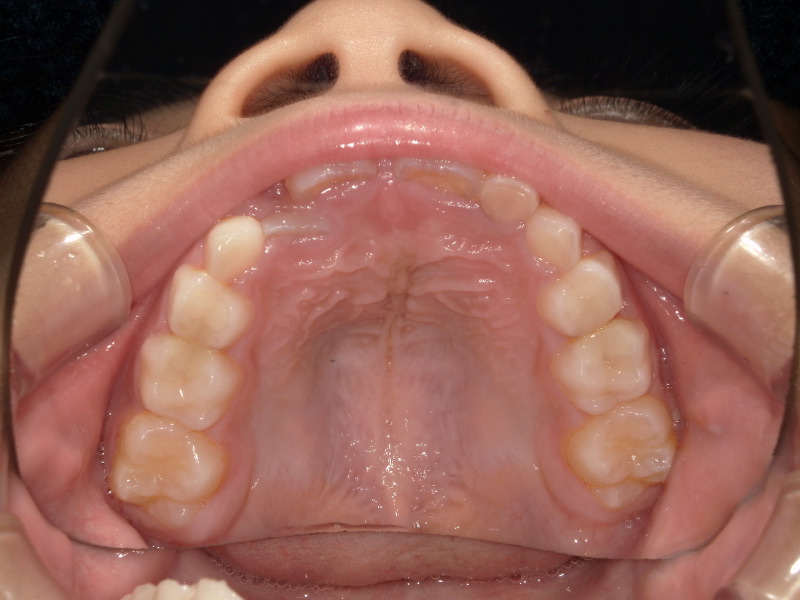

乳歯の時の歯の写真を横から撮った画像です。

下は本来の乳歯の時の噛み合わせの横の写真です。

いつも噛み合わせは上の歯が少し前にありその少し後ろに下の歯が並びます。

上の顎が先に成長し、下の歯は後からグッと成長します。

このままの噛み合わせで成長をすると最終的に反対咬合になる可能性も出てきます。